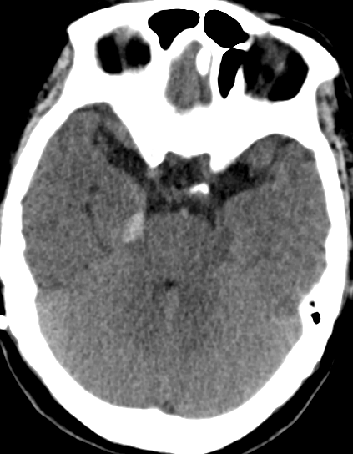

2014-11-28 CT

2015-12-13 MRI

2015-1-30 DSA